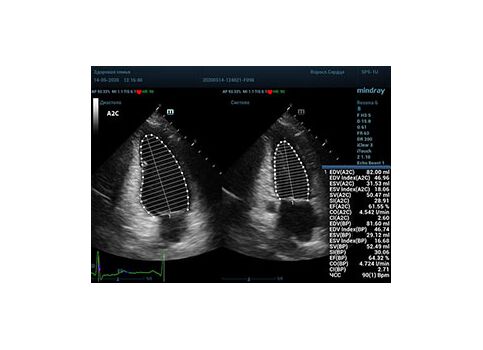

С появлением В режима реализовалась возможность визуализации всех сегментов миокарда из парастернальных и апикальных сечений. Метод Teicholtz в широкой практике сменился методом дисков. Метод дисков, или метод Simpson, позволяет разбить левый желудочек на 20 дисков, с расчетом объема каждого из них. Используя 2 перпендикулярных сечения, апикальные двух и четырех камерное, мы приближаемся к значению реального объема левого желудочка. Исследователь обводит интерфейс эндокард – кровь в фазу диастолы и фазу систолы. Линия простирается от кольца митрального клапана и до кольца митрального клапана, четко разграничивая объем желудочка от предсердия. Для достоверного изменения необходимо использовать ЭКГ канал.

Обводить вручную эти линии занимало много времени, однако результат того стоил. Следующим шагом стало появление Spline технологии, позволяющее расставлять точки и автоматически их соединять. Такой способ планиметрии контура эндокарда значительно сократил время измерения.

Что могут предложить современные приборы? Приборы нашего времени являются мощными вычислительными машинами, способными обрабатывать полученную информацию даже без помощи человека. Система автоматического вычисления фракции выброса – AUTO EF на

приборах серии Resona компании Mindray сделает все за вас. За пару секунд прибор сам отыщет нужную фазу сердечного цикла и произведёт измерение и расчеты, а также покажет график изменения объема в сердечном цикле. От Вас требуется только получить качественное 4С и 2С сечение. Впрочем, прибор всегда оставляет возможность коррекции, если доктор имеет свое мнение на расположение точек планиметрии или момента измерения по ЭКГ каналу.